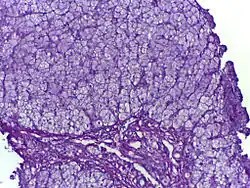

Glycogen storage disease in hepatocytes

SymptomsBiopsy shows either abnormal accumulation or deficit of glycogen

Diagnosis

Micrograph of glycogen storage disease with histologic features consistent with Cori disease. Liver biopsy. H&E stain.

Methods to diagnose glycogen storage diseases include history and physical examination for associated symptoms, blood tests for associated metabolic disturbances, and genetic testing for suspected mutations.[16][45] It may also include a non-ischemic forearm test, exercise stress test, or 12-minute walk test (12MWT).[45] Advancements in genetic testing are slowly diminishing the need for biopsy; however, in the event of a VUS and inconclusive exercise tests, a biopsy would then be necessary to confirm diagnosis.[45]